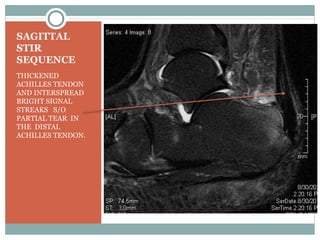

SAGITTAL

STIR

SEQUENCE

THICKENED

ACHILLES TENDON

AND INTERSPREAD

BRIGHT SIGNAL

STREAKS S/O

PARTIAL TEAR IN

THE DISTAL

ACHILLES TENDON.